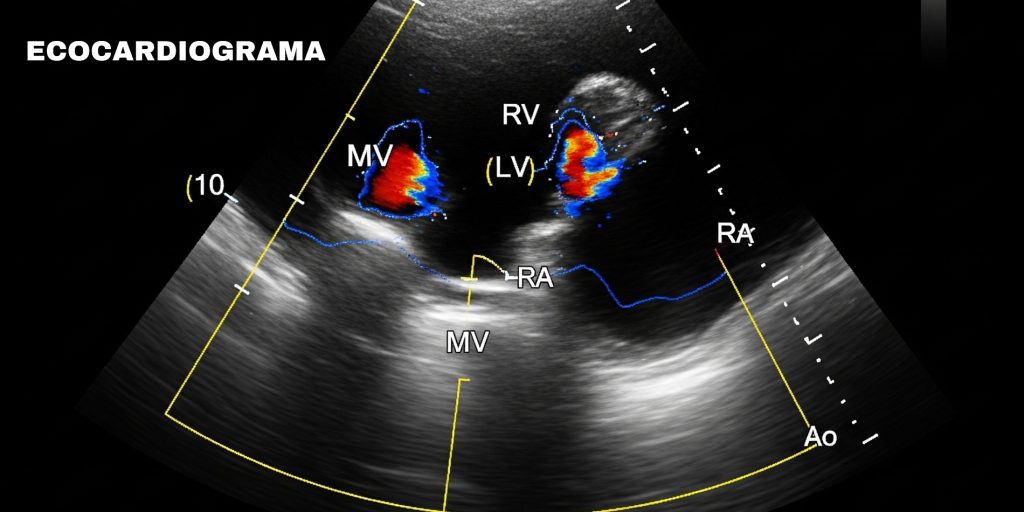

La Importancia de un Diagnóstico Preciso para Tu Corazón

El ecocardiograma permite visualizar en tiempo real la estructura, el funcionamiento y el flujo sanguíneo del músculo cardíaco.